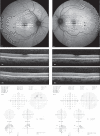

Methods: Data were collected prospectively from all patients attending Manchester Royal Eye Hospital hydroxychloroquine screening service over the audit period. Results of Humphrey visual field tests, spectral-domain optical coherence tomography and fundus autofluorescence were collected as well as data on dose, indication, duration of treatment, and additional risk factors. Cases were identified as having definite, possible, or no retinopathy based on the 2018 RCOphth criteria. The data are not publicly available due to information that could compromise research participant privacy and confidentiality but are available upon request from the corresponding author.

Results: 910 patients attended for screening. 566 were identified as being at risk of retinopathy (543 had been on treatment >5 years, 10 had renal impairment, 12 were on doses of >5 mg/kg/day, and one was concurrently on tamoxifen). The prevalence of HCQ retinopathy was 10/910 (1.09%) of all those screened, and 1.76% of those at risk (10/566). Six patients of those deemed at risk were identified as having definite hydroxychloroquine retinopathy, while four had possible retinopathy.